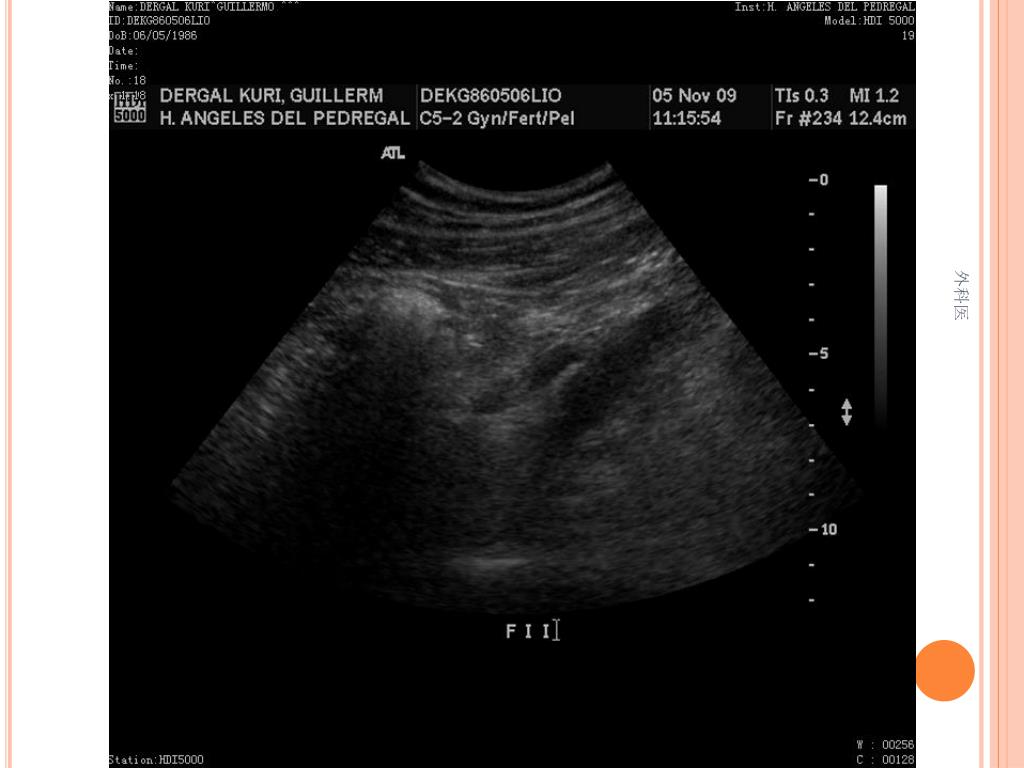

36. PATOLOGIA 外科医

41. PRODUCTO DE RESECCION INTESTINAL: APENDICITIS AGUDA FIBRINOPURULENTA, FIBROSIS PERIAPENDICULAR SEVERA. ILEON TERMINAL Y COLON CON HIPERPLASIA LINFOIDE FOLICULAR Y PERITONITIS AGUDA 外科医